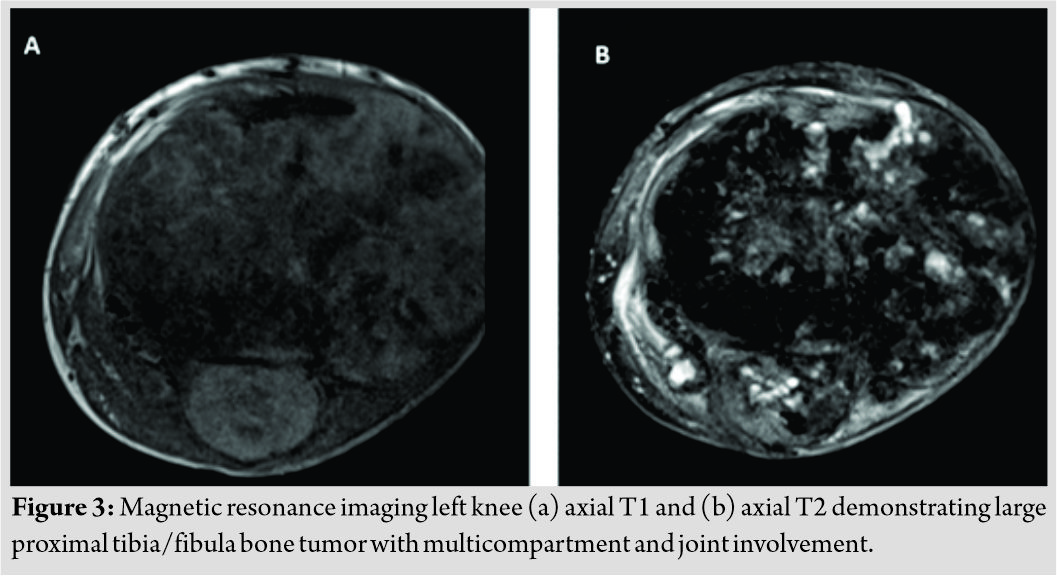

Initial radiographs revealed a large, expansile mass involving the left proximal tibia and fibula with bony destruction and possible intra-articular extension (Fig. 1). It also demonstrated significant soft-tissue extension, mineralization, and periosteal reaction concerning for osteosarcoma. Computed tomography of the chest, abdomen, pelvis, and spine revealed no evidence of metastatic disease. Magnetic resonance imaging revealed a multilobulated, heterogeneous mass measuring 14 cm × 13 cm × 13 cm replacing the left proximal tibia and fibula, with multicompartmental and intra-articular involvement (Fig. 2, 3). It also showed that the distal popliteal neurovascular bundle was posteriorly displaced with full encasement of the anterior tibial artery at the level of the popliteal trifurcation. In addition, the common peroneal nerve was significantly displaced by the tumor and could not reliably be differentiated from the mass. A magnetic resonance angiogram was performed which showed a hypervascular proximal tibial lesion with poor definition of vascular anatomy. A nuclear medicine bone scan was then performed which showed a large expansile mass of the proximal left tibia, fibula, and distal femur with intense radiotracer uptake. The initial radiographic findings were consistent and suggestive of osteosarcoma, and the patient was subsequently scheduled for biopsy.